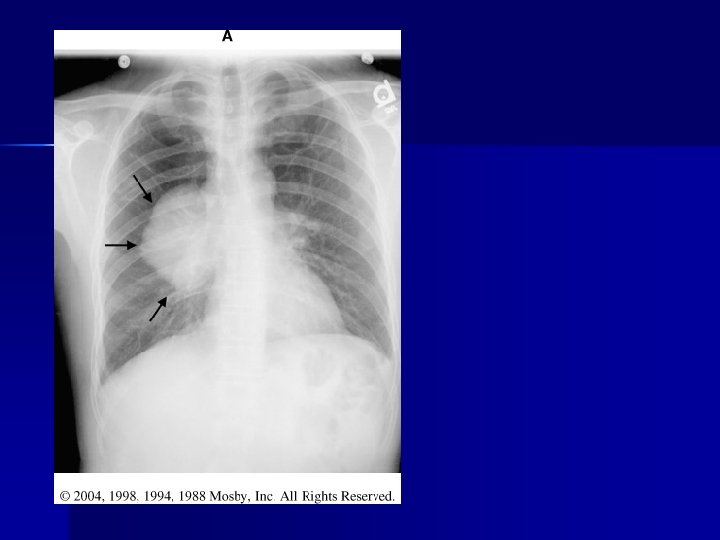

PATHOLOGY NOT ARTIFACT

Name & cause of this?

Evaluating Images What do you think?

n n n Does this show good detail? Is all of the anatomy present? How is the density / contrast?